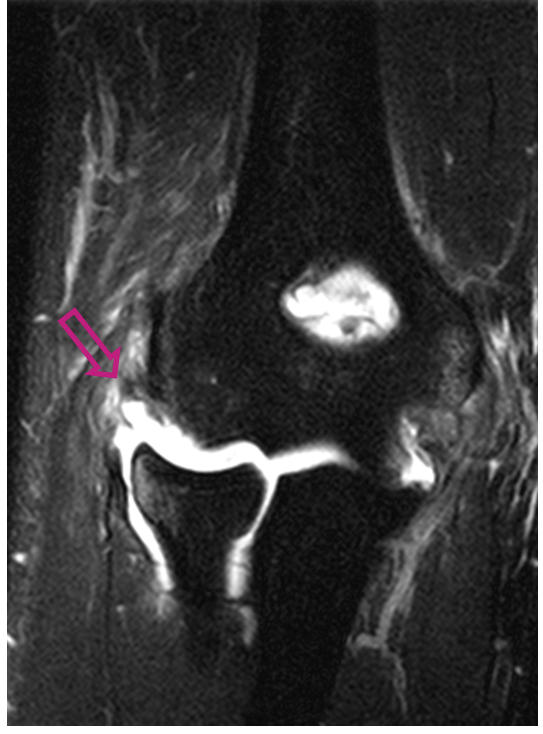

영상 진단: X-ray, MRI, 때로는 CT 스캔을 사용하여 관절의 구조와 손상 정도를 평가합니다.